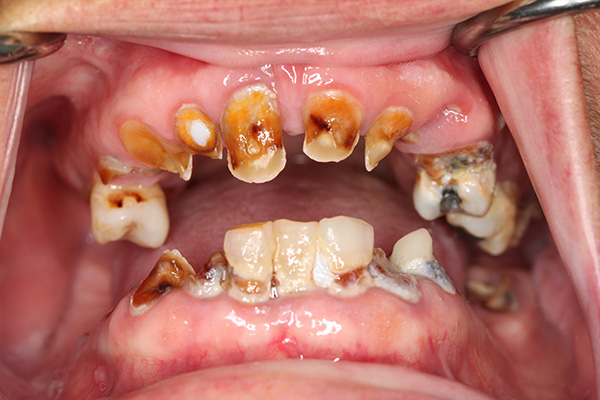

After dealing with years of erosion and stains, this patient came to us to learn more about how to improve her smile. With dental crowns, we were able to restore her teeth with a natural, white and confident smile. We understand that sometimes life prevents us from making our way to the dentist, but this patient was pleased to learn that it's never too late to receive the dental care you need and deserve.